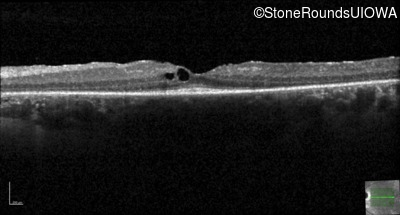

Optical Coherence Tomography - Left -

20/20 -2

Exemplar / OCT Stack